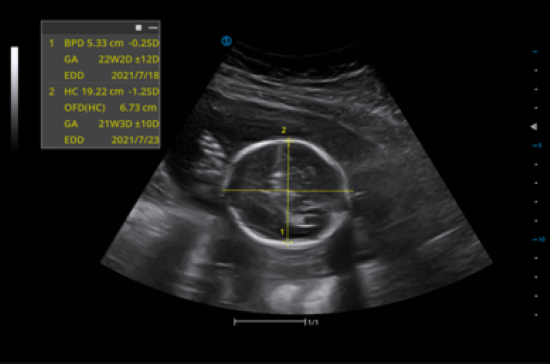

Auto Optimal View

Intelligently identify the standard sections for measuring fatal BPD, FL, AC from the collected cines.

Auto OB

Automatic measurement of the common fetal biometry results such as BPD, FL, HL from the standard examination sections of fetus.